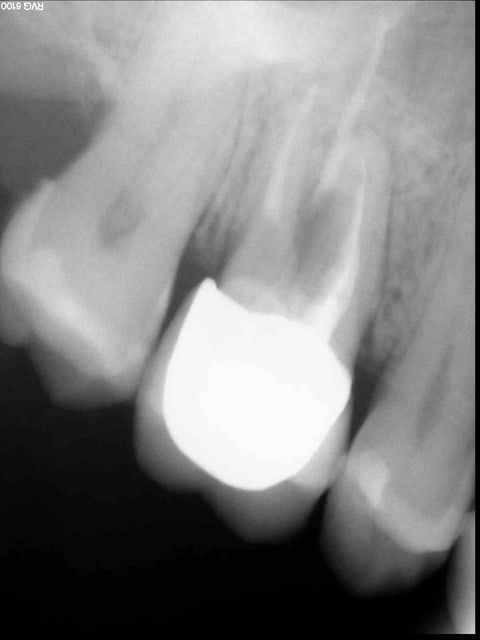

J'ai pas mal hésité sur le titre de ce post , et je vais sans doute m'attirer pas mal de critiques acerbes mais tant pis , j'ose : en fin de matinée , j'ai vue une nouvelle patiente qui arrive avec un dossier sous le bras... elle se plaint d'une 16 couronnée et m'explique que son ancien dentiste (dentiste énergétique ) lui a fait un traitement avec des huiles essentielles sur cette dent parce que "la gencive n'arrivait pas à se coller à l'os"et elle commence à m'expliquer l'historique de sa dent , et comme je ne suivais pas très bien, elle me sort donc son beau dossier . je vous la fais courte : pour cette 16, elle était passée entre les mains d'un endodontiste réputé de Lyon (750 €)en 09/2012 qui a traité cette dent non cariée mais qui présentait une infection radiculaire (que j'ai pu vérifier sur une pano de 2011 ) puis en oct 2012 , la collaboratrice du premier praticien lui pose un IC clavette (dent saine au départ !!)zircone et couronne ceramo zircone ...bio compatibilité oblique bien sur ... total:1200 €, bref en janvier 2013 , elle retourne voir ce praticien avec des douleurs intenses , donc mise sous ATB (tiens tiens !) et un curetage avec lambeau est réalisé ...puis l'épisode des massages avec des huiles essentielles . Cette dent est toujours douloureuse ...Bref ,pour corser l'histoire , je remarque qu'il lui manque la 34 .. et là , elle m'explique qu'on lui a extrait parce que elle bloquait ... sa féminité !!! 34 totalement saine , objectivée sur la pano de 2011, en rotation effectivement . Conclusion de l'affaire : on lui a fait débourser pas loin de 2000 € pour une molaire apparemment à risque ..mais par contre on lui a extrait allègrement une 34 pour une raison plus qu'obscure !!! Voilà j'attends vos réactions et remarques ..je vous joins la radio de cette fameuse 16 ...

Un truc pas net à la furcation..pronostic sombre.. À vue du dossier, te reste plus qu'à demandé un CBCT et conf l'irréversibilité de/des lésions .. C'est quoi qui te déranges ici? Je veux dire dans la prise en charge, hormis le cas 34.

Et ben voilà ... ce que j'attendais arrive .... La patiente est fêlée , elle mange des pierres , et pour finir le tableau elle a des difficultés de fellation ( ça , ça m'a fait bien rire .) et bien sûr nos chers confrères sont irréprochables .. Alors oui j'accuse ! tout d'abord une dent "saine" qui se nécrose : y'a un problème et là je vous rejoins : fêlure , fracture .usure importante .. bref on recherche la cause ... je vous rappelle que l'endo a été faite sous microscope .. à quoi cela sert -il de posséder une tel appareillage si on ne peut objectiver ce genre de problème. Première erreur et à 750 € la patiente est en droit de réclamer une durée de vie de sa dent supérieure à 8 mois , non ? nous avons tous des doutes, des échecs mais un minimum en cas de doute c'est d'en faire part à sa patiente .. c'est sur que ça passe beaucoup moins bien quand elle vient de vous faire un gros chèque ! deuxième erreur (à mon avis !!) l'inlay core à clavette : je vous rapelle que cette dent était saine au départ .l'endodotiste a donc mutilé la dent autant que ça ??? troisième erreur (toujours à mon avis !) la précipitation de poser les éléments prothétiques ..un mois après alors que cette dent présentait une image apicale depuis longtemps ... un petit temps de latence et d'observation m'auraient paru utiles .. Tout ceci est mon avis et je le partage !! à vos claviers acerbes ...

Et si au lieu de focaliser sur la 16 en écoutant la patiente dire du mal de son ex praticien on parlait de la 15 qui semble avoir (à la radio ) une obturation ainsi qu'une micro porte d'entrée en distal inter dentaire